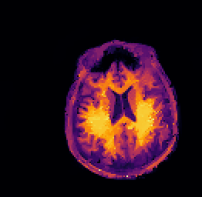

Refer to caption sinogram datafg

Refer to caption deformed ground truthfg Refer to caption deformed ground truthfg

Refer to caption side informationfg Refer to caption side informationfg

Refer to caption ground truthfg Refer to caption ground truthfg

Refer to caption FBPfg

SSIM 61.3%

RD n/a

Refer to caption TVTV\operatorname{TV}fg

SSIM 88.1%

Refer to caption three-stepfg

SSIM 93.3%

RD 6.5%

Refer to caption proposedfg

SSIM 93.6%

RD 3.1%

Figure 5: PET reconstructions with structural MR side information. Filtered back-projection (FBP) and TVTV\operatorname{TV} do not correct motion and yield poor reconstructions. Both the three-step and the proposed method correct the deformation and the reconstruction satisfyingly agrees with the ground truth. We give SSIM and RD values of the reconstructed images and deformation parameters. For FBP and TVTV\operatorname{TV} no deformation was corrected and SSIM is given with respect to the deformed ground truth.

In this experiment we consider PET-MR, where we aim to reconstruct a tracer distribution using a fully sampled T1-weighted MR image of size 144×144144144144\times 144 as side information. The forward operator is modelled by a parallel beam X-ray transform with 200 angles equispaced in (0,π]0𝜋(0,\pi] and 192 bins. The sinogram data were simulated using a ground truth image deformed with respect to the side information through the rigid deformation

ϕrigid(x)=Rθx+b,subscriptitalic-ϕrigid𝑥subscript𝑅𝜃𝑥𝑏\displaystyle\phi_{\texttt{rigid}}(x)=R_{\theta}x+b, (23)

where Rθsubscript𝑅𝜃R_{\theta} is a rotation matrix (12) with angle θ=0.15.7𝜃0.1superscript5.7\theta=0.1\approx 5.7^{\circ} and b=(0.02,0.08)T𝑏superscript0.020.08𝑇b=(0.02,0.08)^{T} is a translation vector.

In this experiment we simulate data based on a dTVdTV\operatorname{dTV}-regularized reconstruction of clinical data, see [28]. The data is an instance of a Poisson random variable with parameter Ax+r𝐴𝑥𝑟Ax+r, where the background r𝑟r is chosen as constant 7 and the forward operator is scaled to about 1.31061.3superscript1061.3\cdot 10^{6} expected counts in the data. Correspondingly, the data fidelity used is the Kullback–Leibler distance (4).

Again, images are in [1,1]2superscript112[-1,1]^{2} and hence the pixel width of the side information is 0.0138¯0.013¯80.013\overline{8}. The resolutions and regularization parameters in Algorithm 2 were chosen as nk=(92,182,362,722,1442)subscript𝑛𝑘superscript92superscript182superscript362superscript722superscript1442n_{k}=(9^{2},18^{2},36^{2},72^{2},144^{2}) and αk=4101(104,103,102,10,1)subscript𝛼𝑘4superscript101superscript104superscript103superscript102101\alpha_{k}=4\cdot 10^{-1}\cdot(10^{4},10^{3},10^{2},10,1). For the TVTV\operatorname{TV} experiment we used αk=4102(104,103,102,10,1)subscript𝛼𝑘4superscript102superscript104superscript103superscript102101\alpha_{k}=4\cdot 10^{-2}\cdot(10^{4},10^{3},10^{2},10,1).

The sinogram data and the deformed image which was used to generate the data are shown in the top row of Figure 5. Furthermore, we show the side information and the ground truth image. In the second row of Figure 5 we show four different reconstructions: the first one obtained through filtered back-projection, the second one utilizing TVTV\operatorname{TV} regularization, the third one using the three-step method (22), and the fourth one being the proposed method. The first two methods, which do not use the side information or correct any motion, exhibit poor image quality due to strong noise in the sinogram. On the other hand, both the three-step and the proposed method correct the deformation and the reconstructions are in very good agreement with the ground truth image.

Quantitatively, the SSIM values for filtered back-projection and TVTV\operatorname{TV} are relatively low whereas they are comparably high for both the three-step and the proposed method, with slightly better values for the proposed method. The same is also true for the relative errors of the computed deformation fields.